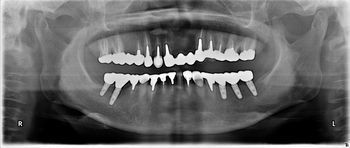

下顎fullインプラント

下顎のフルインプラントです。6本のインプラント(4本では不安です)を埋入して上部構造はスクリュウで固定してます。下の総義歯はみなさんどうしても浮き上がってきて食べにくいです。インプラントを埋入して即時負荷をかけるのはどうかと思いますが、骨と結合した後ならかなり頑丈な上部構造ができて、硬いものでも噛みやすくなります。

●● 様 男性 70代

治療の期間・回数:6か月、10回

治療の価格:150万円/下顎

治療のリスクや副作用:手術後に、痛みや腫れ、出血、合併症などを引き起こす可能性があります。噛む感覚がご自身の歯と異なる場合があります見た目がご自身の歯と異なる場合があります。手術後にメインテナンスを継続しないと抜け落ちる可能性があります。